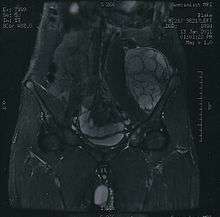

Imaging studies - including radiographs ("x-rays"), computerized tomography (CT), and magnetic resonance imaging (MRI) - are often used to make a presumptive diagnosis of chondrosarcoma.[5] However, a definitive diagnosis depends on the identification of malignant cancer cells producing cartilage in a biopsy specimen that has been examined by a pathologist. In a few cases, usually of highly anaplastic tumors, immunohistochemistry (IHC)is required.

There are no blood tests currently available to enable an oncologist to render a diagnosis of chondrosarcoma. The most characteristic imaging findings are usually obtained with CT.